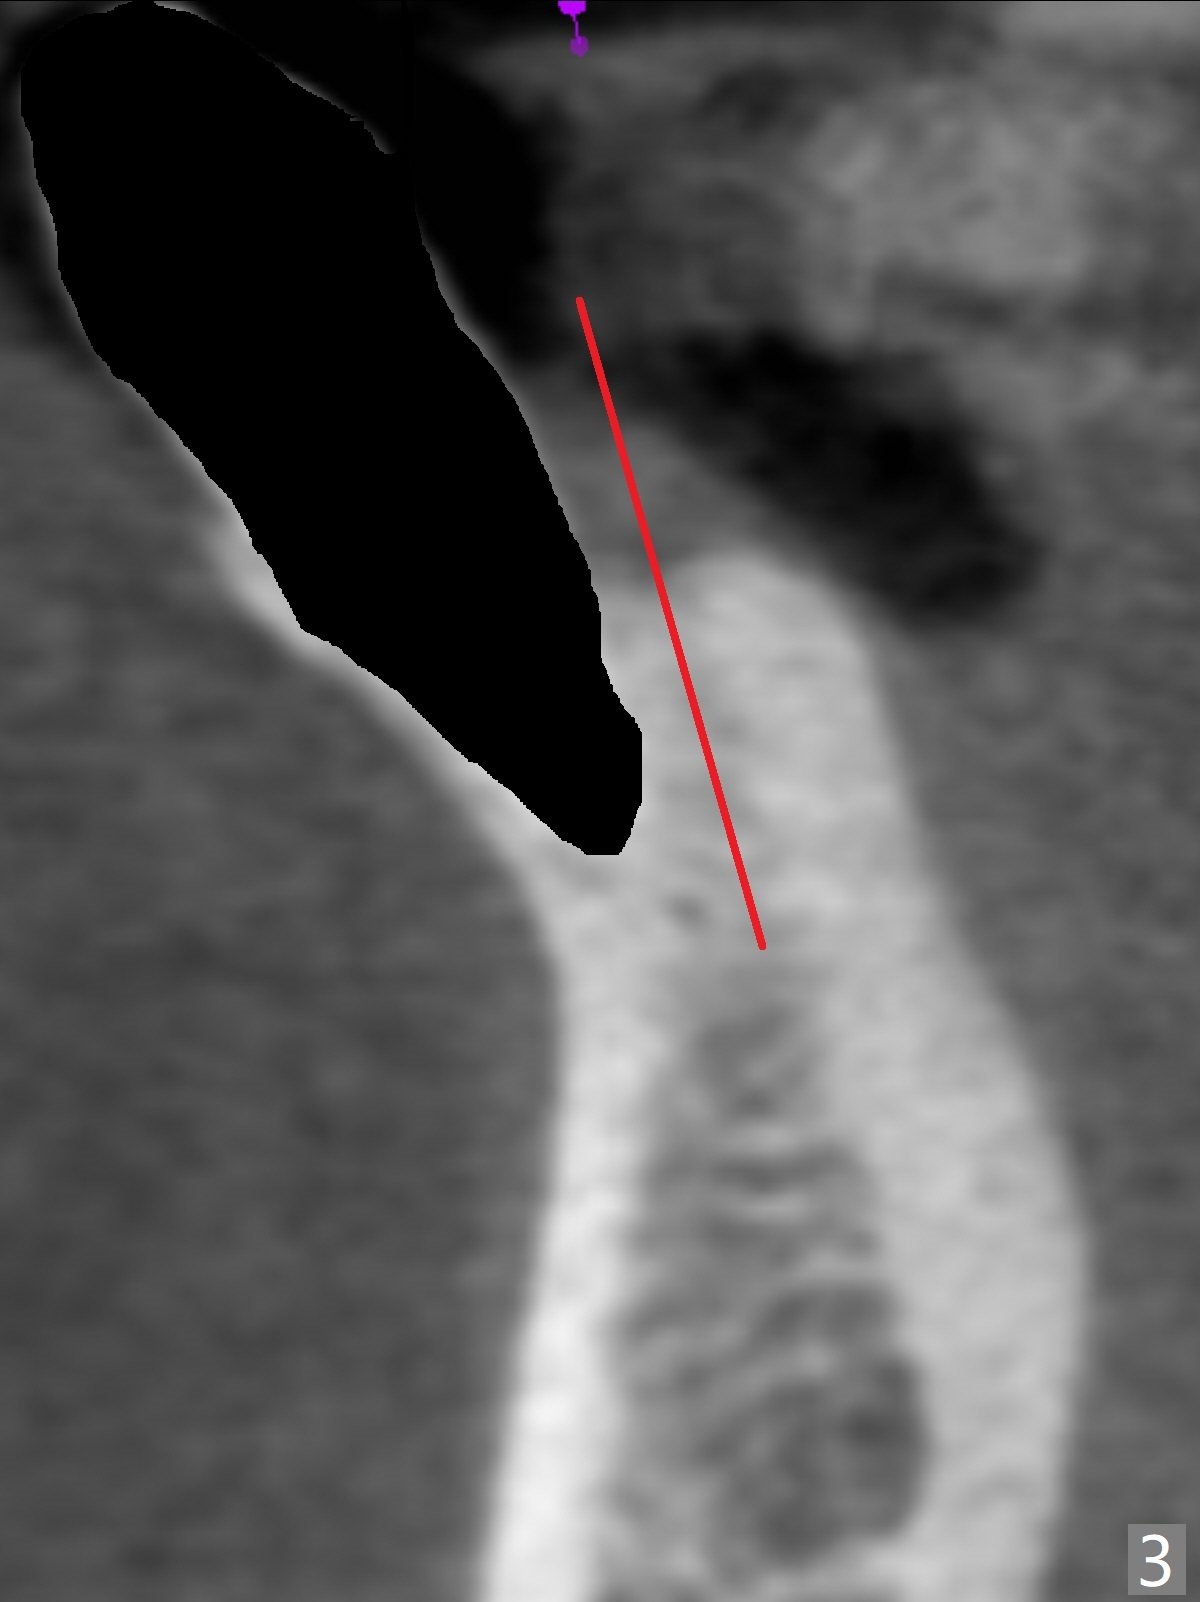

A 44-year-old woman will return for #22/23 (fusion) extraction and implant 2.5 months after one at #25 (Fig.1). If the mesiodistal width of the extraction socket(s) is not particularly wide, one implant will be placed. The tooth #22 seems to be buccally positioned (Fig.2 B). After extraction (Fig.3 black area), initiate osteotomy lingually (red line). Since the spongy bone is not wide buccolingually, a 3 mm implant appears to be appropriate (Fig.4).